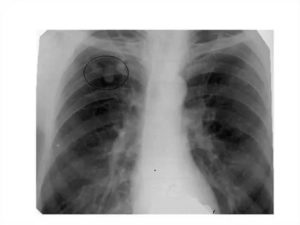

На фото ниже, видно полное истощение организма, в том числе и массы тела.